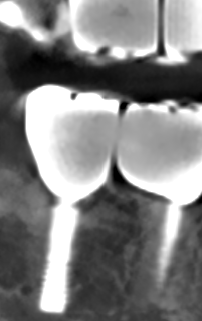

Установка имплантата

Установка имплантата по хирургическому шаблону осуществляется в строго запланированное место. Безопасно. Никаких разрезов, просто прокол в десне

Более 90% осложнений при имплантации никак не связаны с имплантационной системой, а зависят от точности установки имплантата. Любой имплантат должен быть установлен на определенный угол и глубину и чем точнее это сделано, тем меньше проблем будет у пациента. Любой перекос имплантата может вызвать осложнения. Сравните сами. При классической имплантации точность установки имплантата составляет не более 3 мм. Имплантация с шаблоном позволяет установить имплантат с точностью 10 микрон, что в 300 раз точнее, а значит в 300 раз безопаснее.

Примеры работ по имплантации по шаблону без разрезов и швов